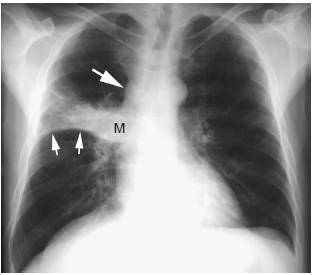

肺不张ct表现图片,肺不张ct图片图解

同一患者胸部ct证实为左肺上叶肺不张(黑箭)

鳞状细胞癌伴支气管阻塞和肺不张

(ct诊断:右上叶占位并阻塞性肺不张,现将片子传上请各位斑竹及同仁阅